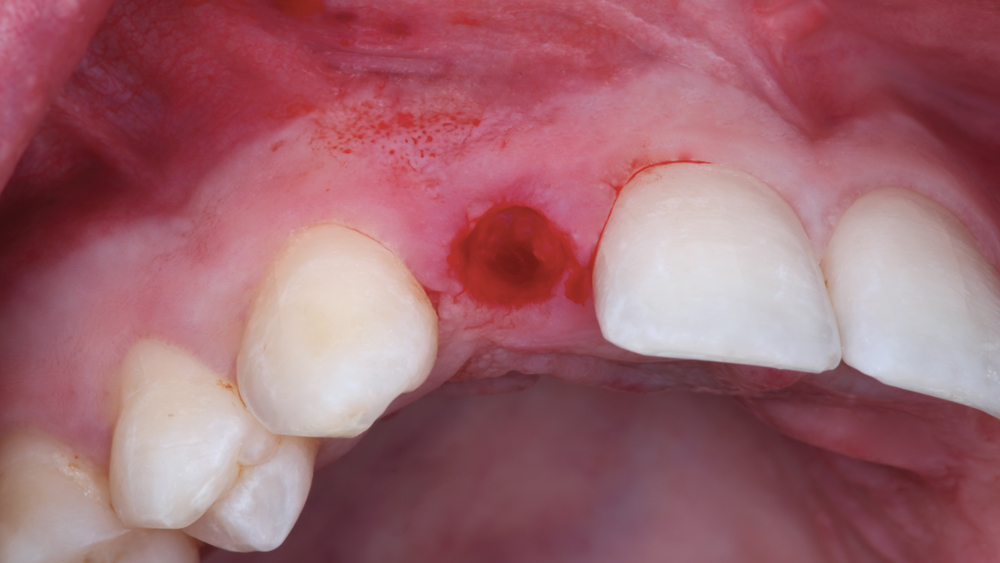

The following case illustrates the efficient, straightforward clinical workflow for placing Hahn Tapered Implants via guided surgery. A digital treatment plan is developed in which a 3.5 mm implant is positioned to support the ideal prosthetic outcome. An immediate provisional crown is designed in concert with the surgical guide and delivered at the time of surgery, helping to produce a predictable, highly esthetic restoration for a demanding case in the smile zone.